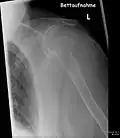

- Aufnahmen pathologischer Frakturen

-

Pathologische Fraktur des Oberarmknochens bei einer Metastase eines Nierenzellkarzinoms -

Pathologische Fraktur des linken Oberarms bei Knochenmetastase einer Patientin mit Brustkrebs -

Ganzkörperknochenszintigramm mit 99mTc-HDP der Patientin mit der Oberarmfraktur aufgrund einer Brustkrebsmetastase